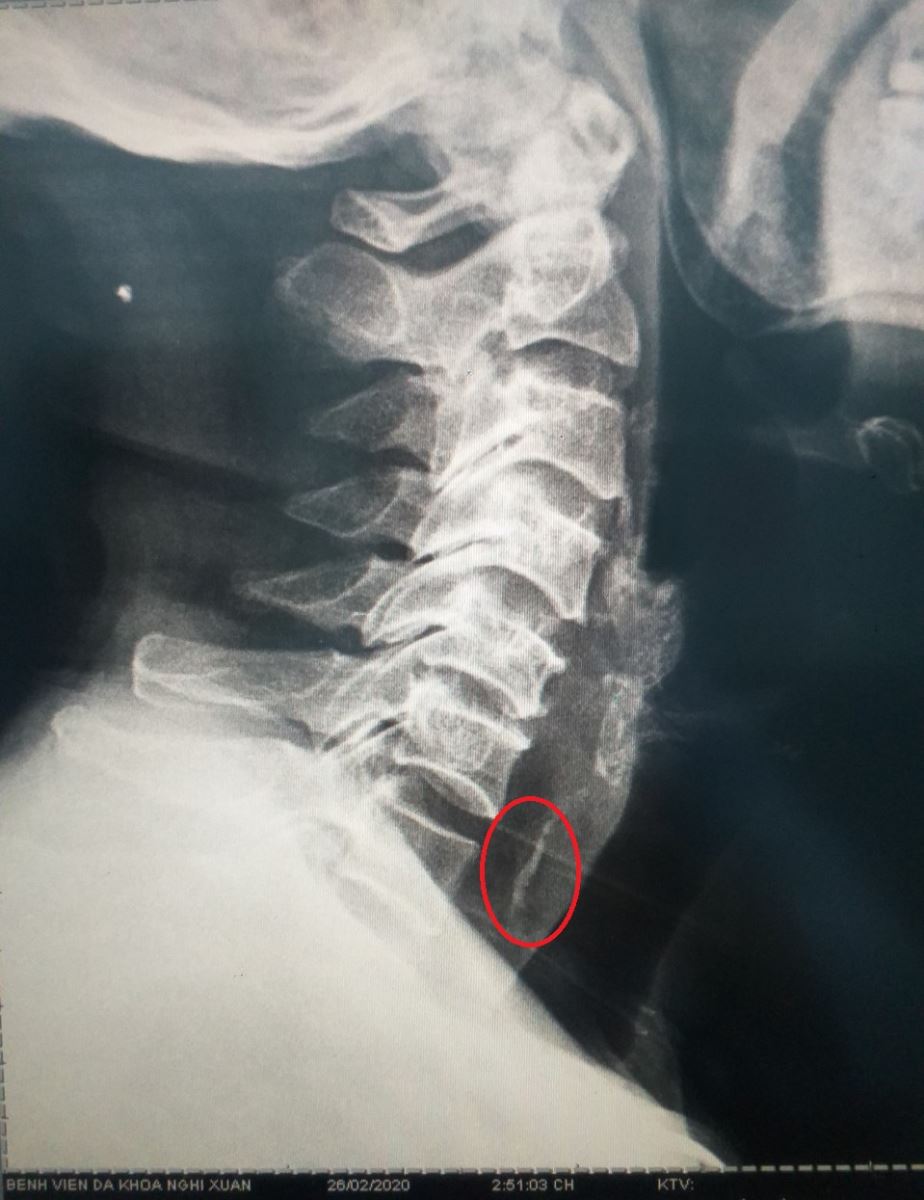

Người nhà đưa bệnh nhân đến bệnh viện đa khoa huyện Nghi Xuân. Khi nhập viện : bệnh nhân tỉnh, nuốt đau, khó nuốt, cảm giác nghẹn thở, dấu hiệu sinh tồn ổn định. Bác sỹ đã chụp X quang vùng cổ ngực thấy hình ảnh dị vật cản quang tương ứng đốt sống cổ VII và chẩn đoán: Dị vật thực quản cổ nghi hóc xương Vịt.

Hình ảnh dị vật cản quang trên phim XQ kỹ thuật số

Bác sỹ Bùi Thị Quỳnh Thơ phối hợp cùng KTV Phan Thị Hải Yến đã tiến hành nội soi gắp dị vật là mảnh xương kích thước 3cm, 3 cạnh. Trong quá trình làm thủ thuật bệnh nhân không tiến hành được phương pháp nội soi gây mê vì bệnh nhân tiền sử điều trị bệnh đợt cấp bệnh phổi tắc nghẽn mạn tính dị ứng với hầu hết các loại kháng sinh và ngay cả Solumedrol. Sau gắp xương bệnh nhân khỏe, nuốt giảm đau, cảm giác dễ chịu . Mạch , huyết áp, hô hấp ổn định.